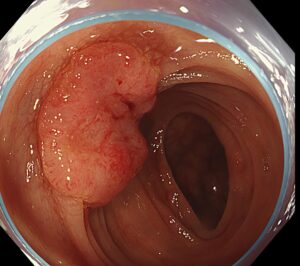

ESD瘢痕上に発生した早期胃癌の内視鏡切除の1例